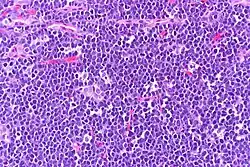

| Burkitt's lymphoma, touch prep, Wright stain | |

The tumor consists of sheets of a monotonous (i.e., similar in size and morphology) population of medium-sized lymphoid cells with high proliferative and apoptotic activity. The "starry sky" appearance seen[22] under low power is due to scattered tingible body-laden macrophages (macrophages containing dead apoptotic tumor cells). The old descriptive term of "small non-cleaved cell" is misleading. The tumor cells are mostly medium in size (i.e., tumor nuclei size similar to that of histiocytes or endothelial cells). "Small non-cleaved cells" are compared to "large non-cleaved cells" of normal germinal center lymphocytes. Tumor cells possess small amounts of basophilic cytoplasm with three to four small nucleoli. The cellular outline usually appears squared off.